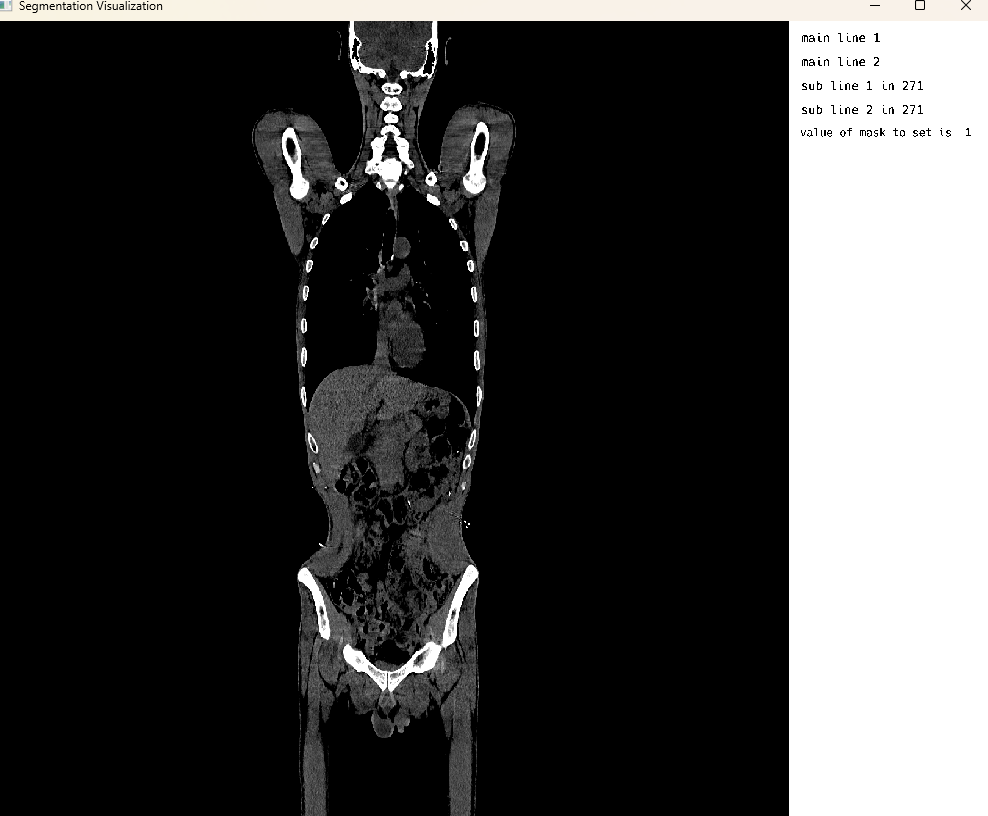

Single Image Display: CT Modality Visualization

This cell visualizes a CT (Computed Tomography) scan in single image mode. The MedEye3d package displays the medical image data, showing the CT scan in an interactive 3D view. Similar to the PET visualization, crosshair rendering is currently only supported in multi-image display mode.

using MedEye3d

medEyeStruct = MedEye3d.SegmentationDisplay.displayImage(ctImageArg) #singleImageDisplaySingle Image Mode: Dynamic Supervoxels From HDF5